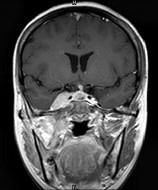

问题 女,34岁。右侧听力下降,耳鸣2个月。MRI平扫及增强扫描如图示,最可能的诊断是()

选项 A.鼻咽癌 B.脑膜瘤 C.神经源性肿瘤 D.动脉瘤 E.未见异常

答案 A